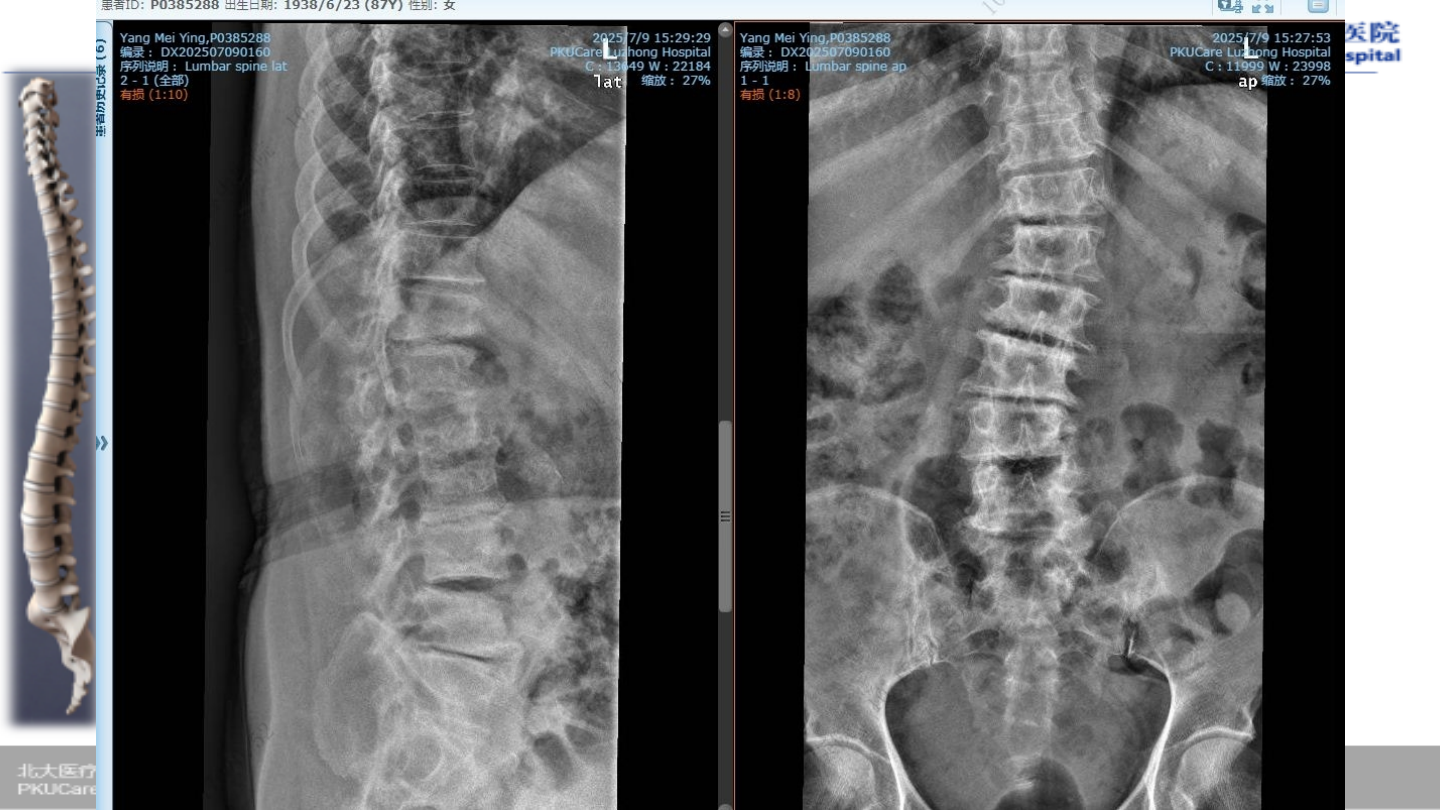

术前

X-ray